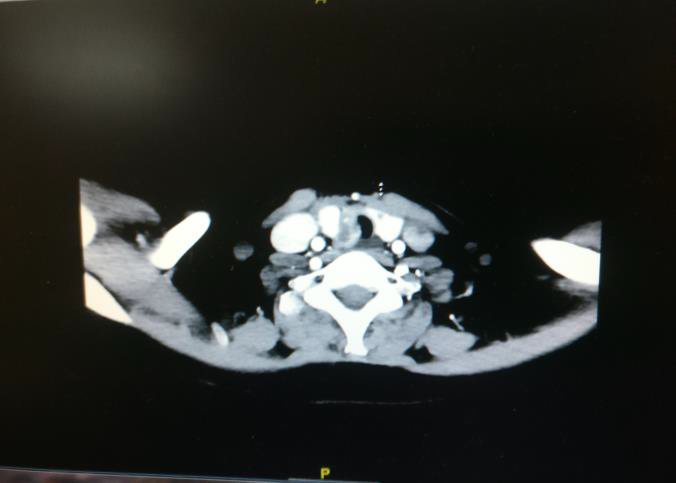

Fig 3: Contrast enhanced CT (axial view) image showing tumour involving the right lobe of thyroid with extrathyroidal extension in to trachea right lateral wall